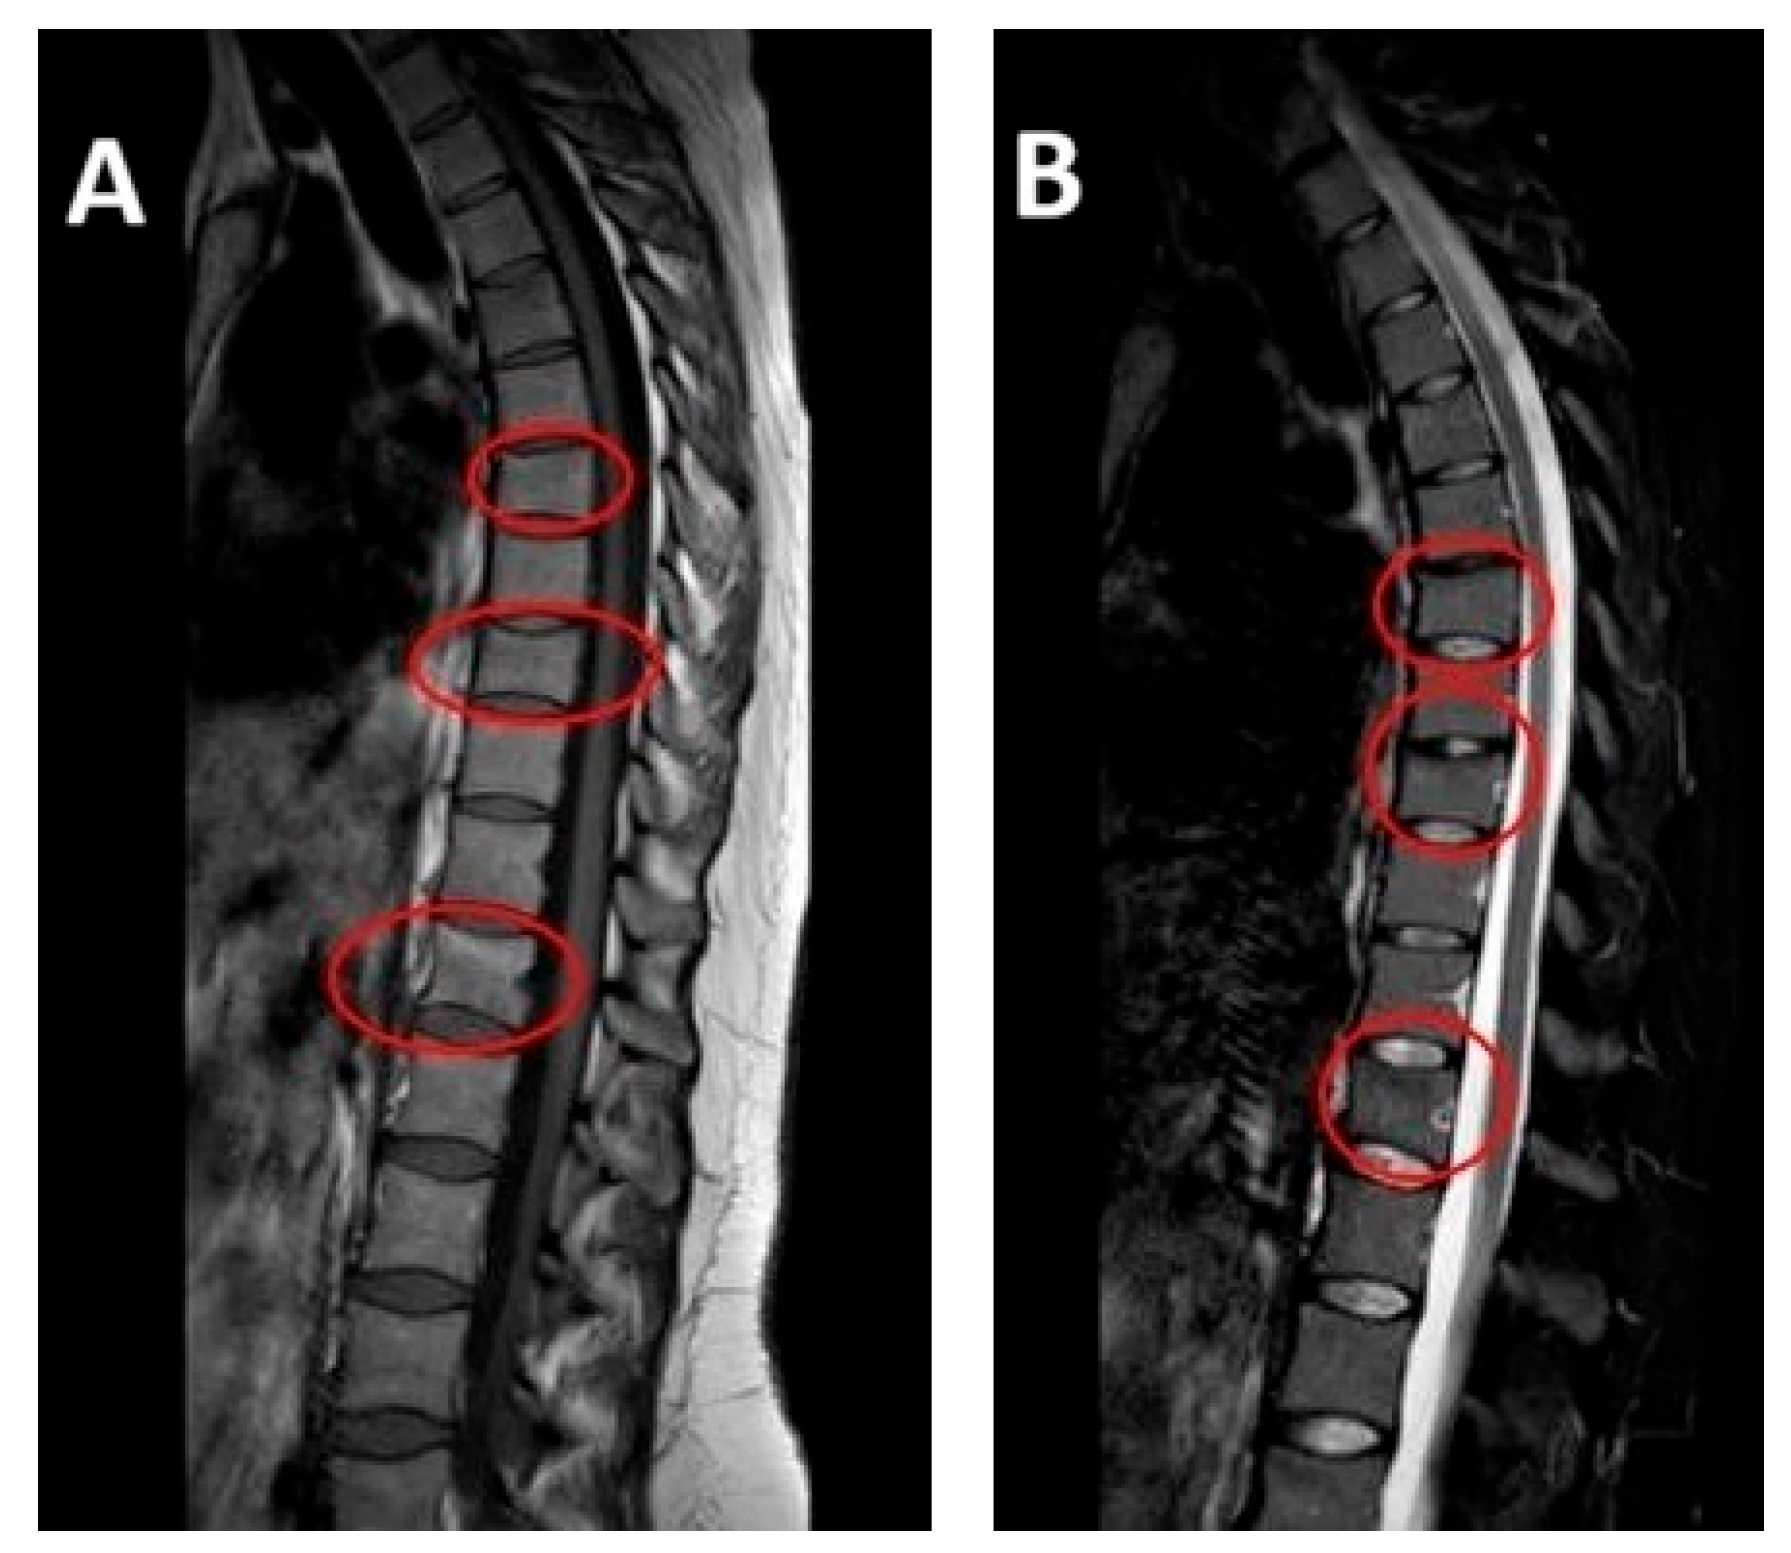

After initiating conservative treatment, the MRI after 90 days was carried out and the results showed a complete disappearance of the vertebral compression fractures. All previously identified fractures were stabilized and the previously noted edematous band in the spongy part of the vertebral body had disappeared (Figure 2).

Figure 2. MRI at follow-up (April 2024, at four-month postpartum follow-up): repeat sagittal MRI showing resolution of edema and stabilization of previous vertebral compression fractures. Vertebral alignment is preserved with no evidence of new pathology. Subfigure (A) on the left shows T1-weighted sequence on the left. Subfigure (B) shows T2-weighted sequence on the right.